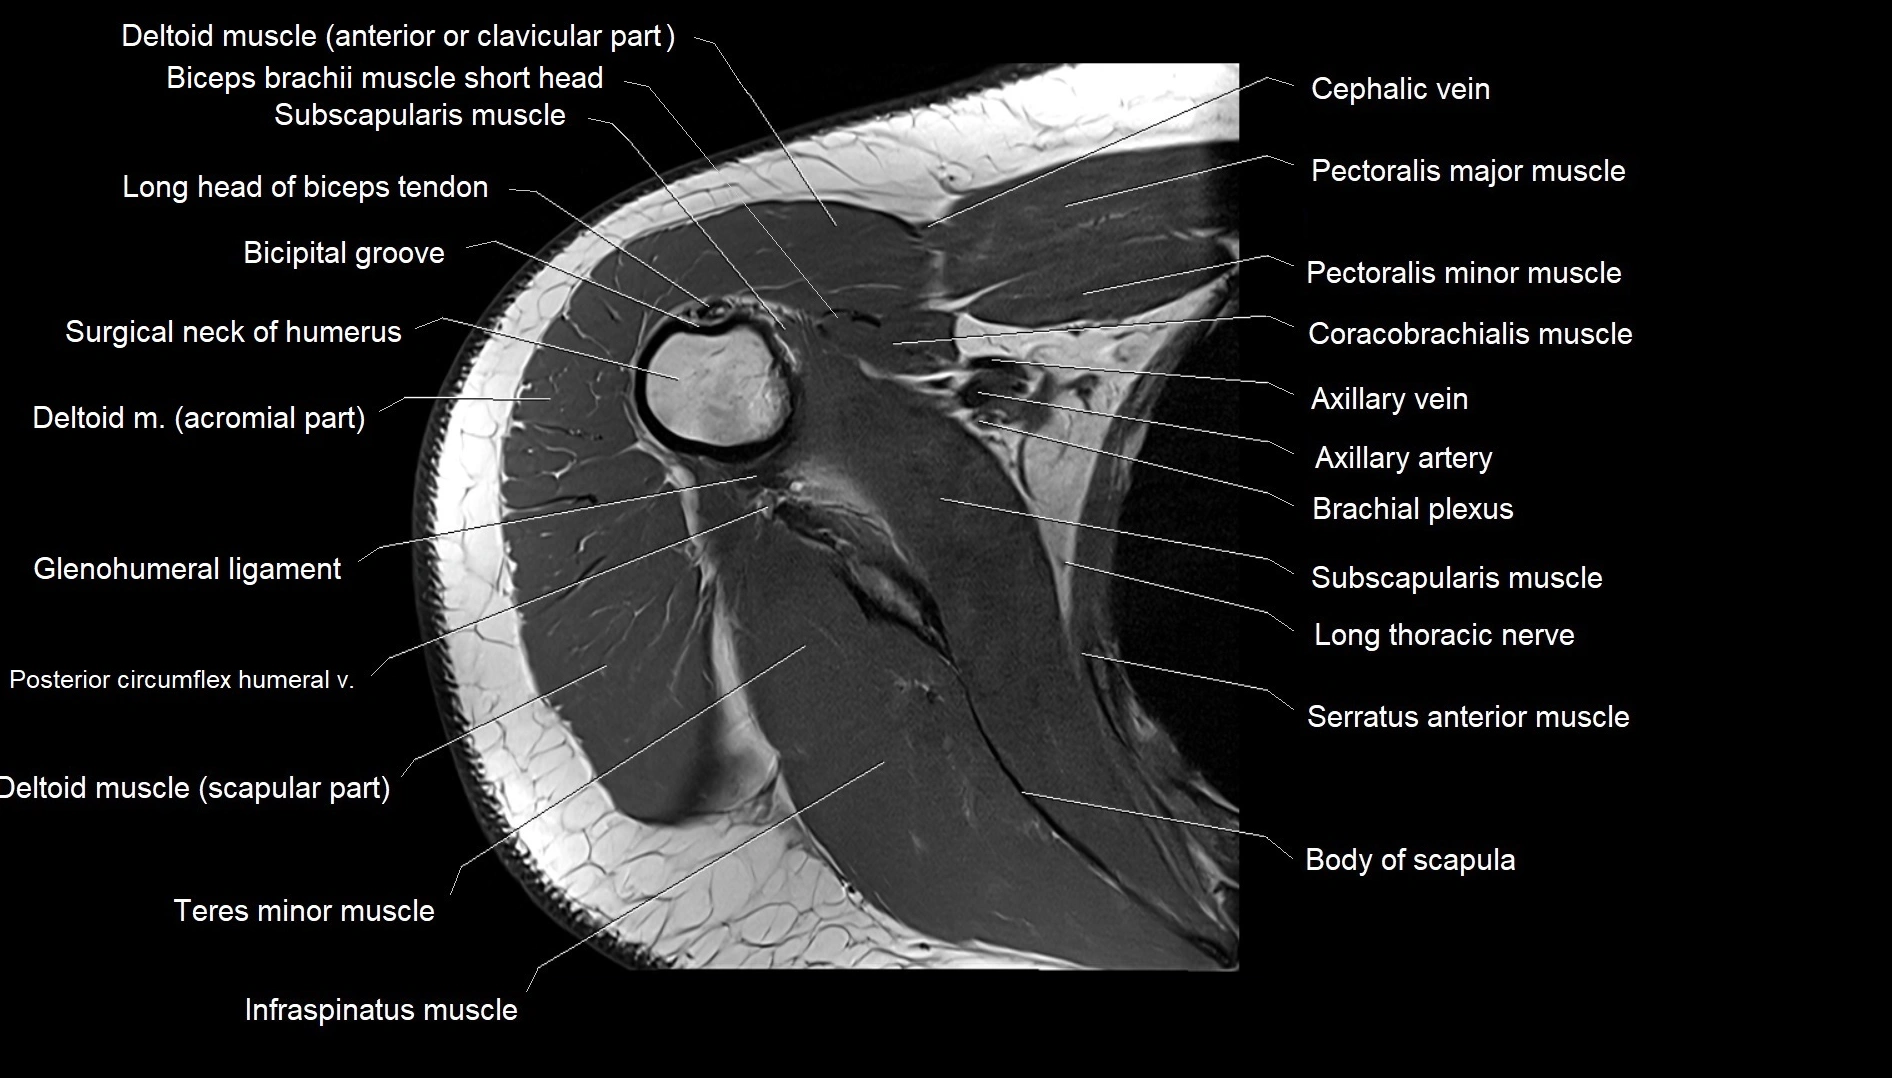

MRI images

image